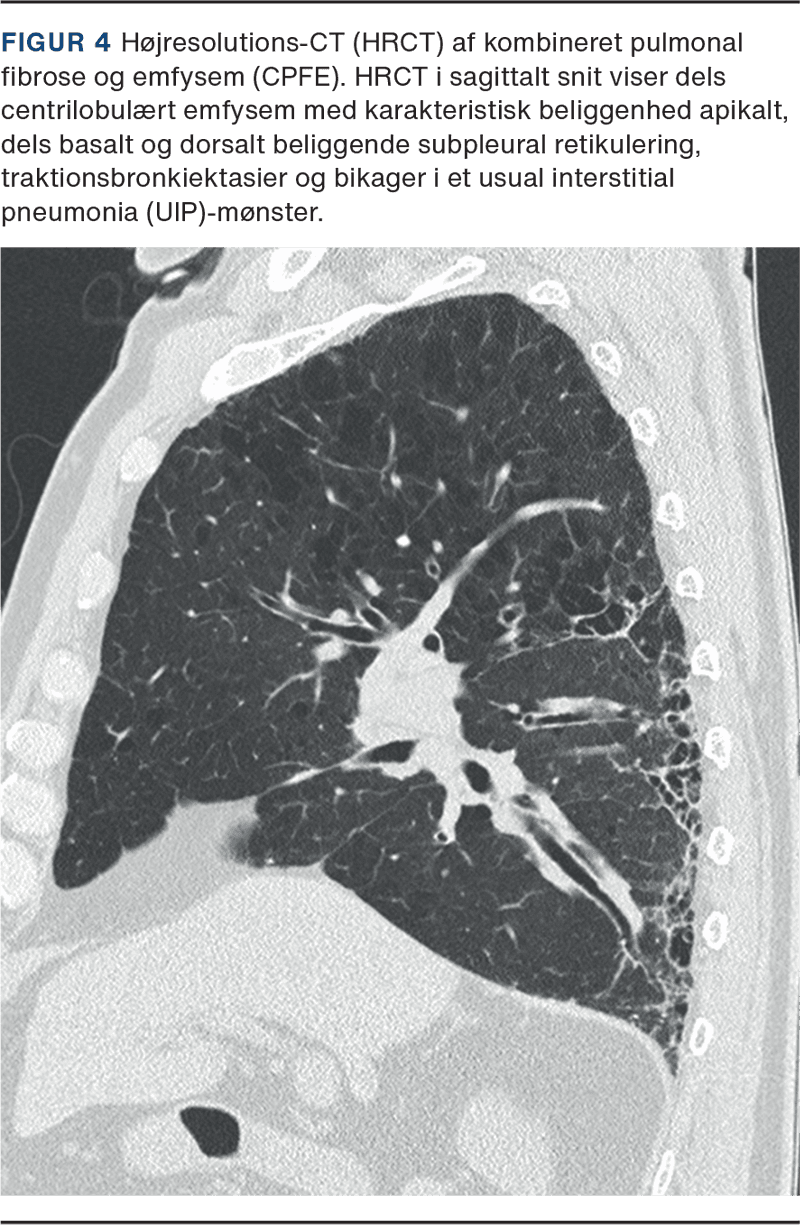

HRCT viser karakteristisk kombination af paraseptal og centrilobulær emfysem i de øvre lungezoner og variable mønstre af fibrose (både radiologisk og histologisk), typisk med UIP-mønster i de basale lungefelter (Figur 4). Radiologisk kan det være vanskeligt at skelne CPFE fra diskrete fibrotiske forandringer i relation til emfysem, der betegnes som airspace enlargement with fibrosis (AEF). AEF er et radiologisk mønster, der histologisk korresponderer til smoking-related interstitiel fibrosis (SRIF), en rygerelateret interstitiel fibrose karakteriseret ved ensartet, mild fibrose og pigmenterede makrofager uden det typiske histologiske UIP-mønster [25].